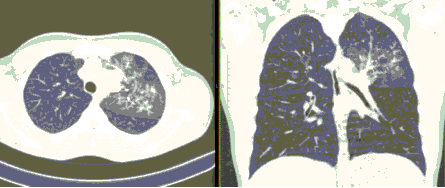

4.3. ЛУЧЕВАЯ ДИАГНОСТИКА COVID-19

Методы лучевой диагностики применяют для выявления COVID-19 пневмоний, их осложнений, дифференциальной диагностики с другими заболеваниями легких, а также для определения степени выраженности и динамики изменений, оценки эффективности проводимой терапии.

КТ имеет высокую чувствительность в выявлении изменений в легких, характерных для COVID-19. Применение КТ целесообразно для первичной оценки состояния ОГК у пациентов с тяжелыми прогрессирующими формами заболевания, а также для дифференциальной диагностики выявленных изменений и оценки динамики процесса. КТ позволяет выявить характерные изменения в легких у пациентов с COVID-19 еще до появления положительных лабораторных тестов на инфекцию с помощью МАНК. В то же время, КТ выявляет изменения легких у значительного числа пациентов с бессимптомной и легкой формами заболевания, которым не требуется госпитализация. Результаты КТ в этих случаях не влияют на тактику лечения и прогноз заболевания при наличии лабораторного подтверждения COVID-19. Поэтому массовое применение КТ для скрининга асимптомных и легких форм болезни не рекомендуется. При первичном обращении пациента с подозрением на COVID-19 рекомендуется назначать КТ только при наличии клинических и инструментальных признаков дыхательной недостаточности (SpO2 < 95%, ЧДД > 22).

4. Все выявляемые при лучевых исследованиях признаки, включая КТ-симптомы, не являются специфичными для какого-либо вида инфекции и не позволяют установить этиологический диагноз. Вне клинической (эпидемической) ситуации они не позволяют отнести выявленные изменения к пневмонии COVID-19 и дифференцировать их с другими пневмониями и невоспалительными заболеваниями. Данные лучевого исследования не заменяют результаты обследования на РНК SARS-CoV-2. Отсутствие изменений при КТ не исключает наличие COVID-19 и возможность развития пневмонии после проведения исследования.

15. Рекомендации по формированию описаний и оценке изменений в легких и ОГК при имеющейся/подозреваемой пневмонии COVID-19 представлены в Приложении 1.